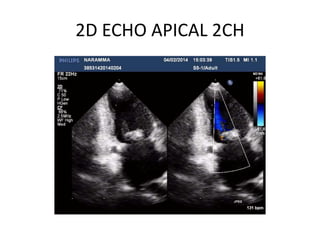

2D ECHO APICAL 2CH

COLOR DOPPLER/FOR MR